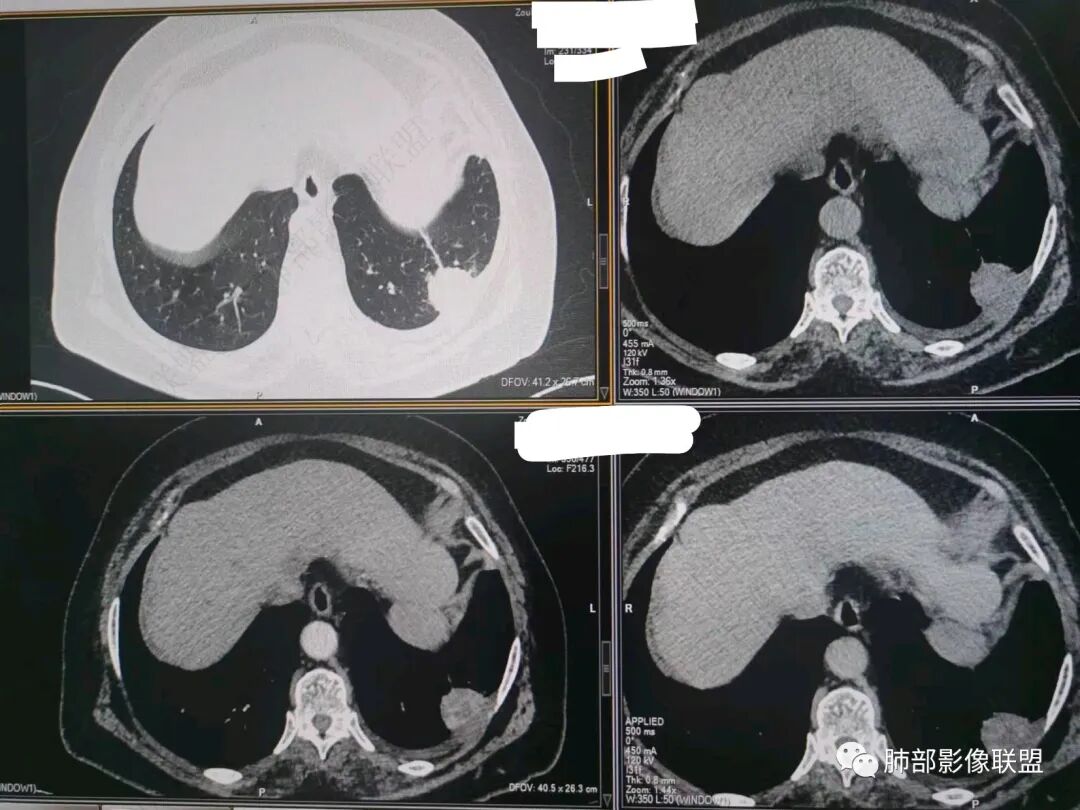

秦化君:左肺下叶外基底段胸膜下软组织密度结节性,边缘毛糙与血管相连,密度不均,增强后病灶内边界不清低密度区,胸膜栽桩,少量胸腔积液。考虑恶性病变,腺癌可能。真菌待排。

谢加平:老年女性,慢性咳嗽,咳白痰史,左肺下叶后基底段胸膜下肿块,类圆形,边界清膨隆,密度不均匀,低强化及小灶性坏死,坏死轮廊不清,胸膜下栽赃明显,左侧胸腔少量积液,向胸壁肌侵犯,另肿块近心侧见支指套征,粘液低密度,支持恶性,粘液腺Ca,经皮肺穿刺活检明确诊断。

361度:老年女性,发热,胸部CT示左下肺胸膜下结节影,血管集束,毛棘,密度不均,胸膜栽赃,少量胸腔积液,不均匀强化,坏死边界不清,肿标轻微升高,考虑恶性,鳞癌合并感染。

红星:老年女性患者。胸膜下结节病变,明显的膨胀,并局部侵犯胸膜,增强明显的强化。病灶周围带有局灶的渗出性改变以及条索上的影。考虑腺癌的可能性大,鉴别结核肉芽肿性病变。

宇宙:左肺下叶胸膜下球形肿块,边界尚清,局部平直,局部膨隆,内侧缘长索条,胸膜栽赃,轻度不均匀强化,其内坏死边界欠清,左侧胸水,考虑腺癌,鉴别放线菌。

袁媛:左肺下叶胸膜下球形肿块,宽基底连于胸膜下,胸膜栽赃,边缘膨隆,有血管供应,增强有强化,考虑腺癌。

songml:老年女性,反复咳嗽咳痰胸闷4年,加重伴发热一周。左肺下叶后基底段胸膜下肿块影,密度较均匀,边缘较清,侵及胸膜下脂肪间隙。考虑恶性病变,腺癌可能,鉴别真菌感染。

人生海海:左肺下叶不规则形软组织密度影,膨隆生长,边缘清楚,分叶,棘突征,支气管截断,血管纠集,病灶轻度强化、内多发坏死,左侧少量胸腔积液,考虑粘液腺癌,鉴别肺脓肿。

位移:老年女性,左肺下叶肺胸膜下团块影,边界清、毛糙,膨隆,内密度不均,不均匀强化,内见坏死,胸膜栽赃,胸腔少量积液,首先考虑恶性肿瘤,低分化腺癌,鉴别小细胞癌,炎性假瘤。

赖晓宇:膨隆,浅分叶,支气管截断,内部坏死边界不清,胸膜受累,胸腔积液,考虑恶性。

许慧良:老年女性患者,左肺下叶后基底段胸膜下结节影,边界清楚,密度不均匀,内部有低密度影,边缘有结节颗粒感,对胸膜有黏连牵拉感,考虑恶性,腺癌可能。

笑微微:左肺下叶外后基底段见结节影,密度不均,边缘欠光整见浅分叶及棘样突起,病灶与相邻胸膜分界不清并见胸膜不均匀性增厚,增强呈不均匀强化,左侧见少量积液。考虑腺癌,鉴别结核。

放射线:左肺下叶后基底段胸膜下肿块,边缘膨隆,密度不均匀,内见低密度坏死,胸膜栽赃,左侧胸腔少量积液,考虑恶性,腺癌?鉴别放线菌,OP伴脓肿。

仲夏:老年女性,咳嗽咳痰近4年,左肺下叶胸膜下类圆形肿块,内侧绳索征,内部密度不均匀,可见坏死,周围小空泡,小叶间隔增厚,胸膜下积液,轻度强化,NSE、细胞角蛋白酶19片段高,考虑恶性肿瘤,腺癌?